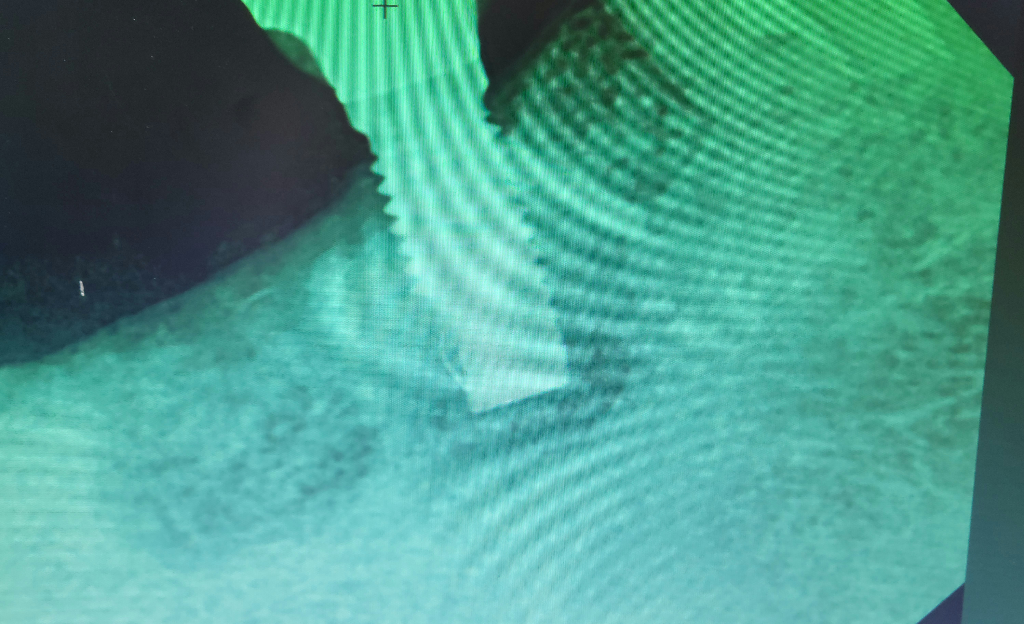

범랑아세포종으로 임플란트 하고 주위염으로발치

발치한 옆에 임플란트 잇몸 색상이 이상해요.

잇몸이 안좋은건가요? 재발도 걱정됩니다

x ray 사진에서는 임플란트 한 치아 주위 뼈 상태는 정상적인 것으로 보입니다. 잇몸 색깔만으로는 정확히 알 수 없으니 기다려 보는 것을 추천합니다. 물론 범랑아세포종이 재발할 가능성은 있지만 지금 x ray 사진상으로는 재발 소견 확인할 수는 없습니다.

엑스레이 상으로는 잇몸색상을 알수 없습니다. 아마도 시간이 지나면서 잇몸이 퇴축되면서 임플란트의 나사선시 비춰보이는게 아닐까 생각됩니다.

임플란트 주위에 염증이 생긴 것으로 보여집니다. 치과 방문 후 치료를 할 수 있는지에 대해서 판단을 받아보셔야 할 것으로 보입니다. 치료가 가능한 수준의 염증이라면 치료시에 잇몸 색이나 증상이 사라질 것으로 보이나 염증이 너무 심하다면 임플란트를 한 부분을 제거해야 합니다.

발치를 하게 되면 해당부위의 골밀도가 낮기 때문에 사진상으로 음영을 보일수 있습니다.